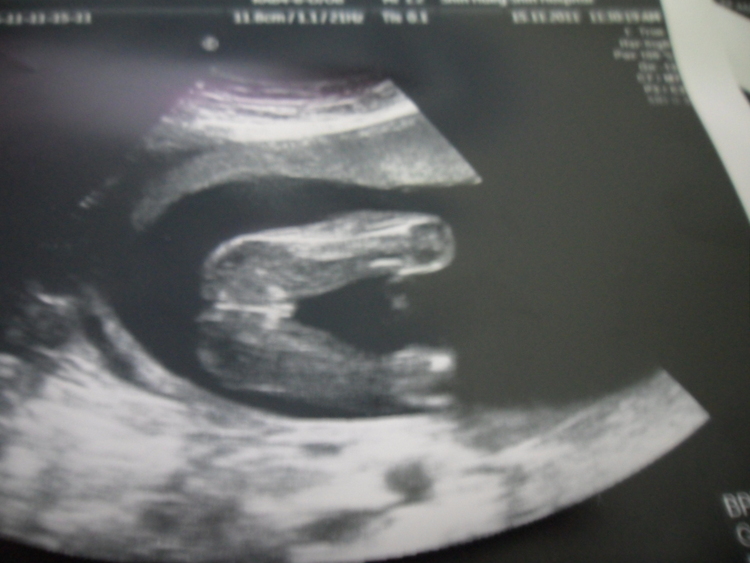

我目前懷孕19週六天..之前去照都因為位置關係所以照不到性別..今天去照超音波醫生說是女生...請問這樣就真的確定是女生了嗎??請有經驗的媽咪幫我看一下..謝謝喔^^

寶寶的腳開很大特徵也很明顯,應該是妹妹沒錯!!

我家小龍女當初雙腳開的角度還不到板水家寶寶的1/2咧!!